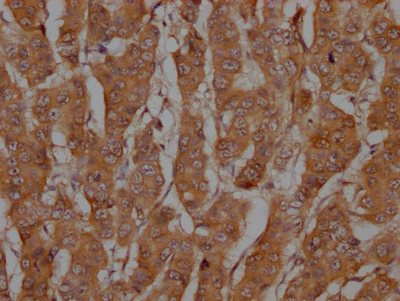

IHC image of CSB-RA286668A0HU diluted at 1:100 and staining in paraffin-embedded human breast cancer performed on a Leica BondTM system. After dewaxing and hydration, antigen retrieval was mediated by high pressure in a citrate buffer (pH 6.0). Section was blocked with 10% normal goat serum 30min at RT. Then primary antibody (1% BSA) was incubated at 4℃ overnight. The primary is detected by a Goat anti-rabbit IgG polymer labeled by HRP and visualized using 0.05% DAB.